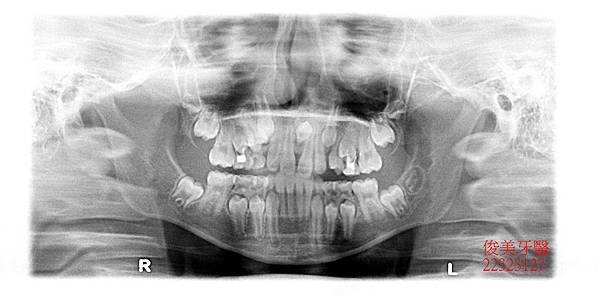

此位患者的咬合狀況為反咬,也就是所謂的戽斗咬合,家長於門診中表示,希望可以改善孩子的狀況。

在醫師的建議下已將門牙中間的多生牙做手術性拔除....並待傷口癒合..

經拍照記錄原始狀況..

患者的上顎犬齒也一直長不出來。